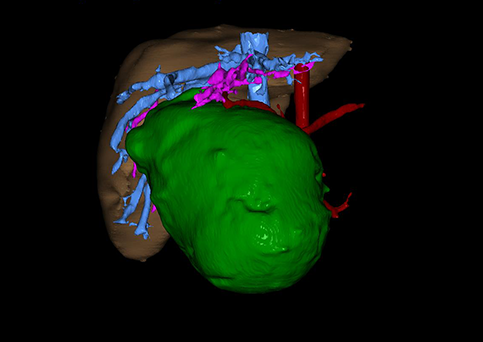

10、三维重建虚拟肝脏、胆道显像技术

三维虚拟肝脏技术是在二维影像学资料如CT等图像的基础上,通过三维重组软件和工具,比如青岛大学附属医院与海信医疗集团联合自主研发的海信计算机辅助手术系统(Hisense Computer Assisted Surgery,Hisense CAS),目前已投入临床并指导实际应用,利用该类系统对二维影像学的数据资料进行三维立体分析,重组形成立体的、有空间结构的、虚拟的肝脏三维图像。这项技术较传统的二维平面成像技术,有着明显的优势,3D虚拟肝脏技术可以构造出一个虚拟的、可视化的肝脏模型。通过对这种模型的观察,可以很容易地分辨出肝脏器官的组织结构、解剖特点,直观研究肝外胆总管的形态差异,明确肝内胆管的形态、走形、是否合并扩张、狭窄及结石,胰胆管合流的形态及共同通道内是否有狭窄、扩张和结石等病变情况,预先规划处理可能合并存在的肝内胆管扩张、狭窄或其他复杂胆道畸形,清晰地显示肝内脉管系统,包括门静脉、肝动脉及肝静脉的走行、分支,并可多角度、全方位观察病变胆道与其周围重要血管尤其是伴行的门静脉之间的解剖关系,大大提高了外科医师在术前对肝脏内部各管道结构及其变异判断的精确性和可靠性,精准地对病变进行判断和评估,还可根据患者自身的病变特点,制定出合理、个体化的手术方案,最大限度地降低术中和术后并发症发生率,并术中导航实时指导手术,提高手术的精准性和成功率。

图10:先天性胆管扩张症囊肿型三维重建虚拟肝脏、胆道显像

a 图为术前二维CT扫描图像,箭头所示为肝内胆管扩张;b 图为CT经多平面重组技术(MPR)图像后处理所得的重建图像,可显示胆总管明显扩张合并肝内胆管扩张;c 图为MRCP显示胆总管呈囊柱状扩张,直径>1 0 cm,伴肝内胆管扩张;d 图示Hisense CAS三维重建清晰显示肝脏、胆道系统及其与门静脉、肝动脉、肝静脉等之间的空间解剖关系;e 图示Hisense CAS可从任意角度以不同脏器组合显示,明确胆道系统与其伴行的门静脉系统的空间解剖关系;f 图示胆道系统立体形态及与肝脏整体的空间关系,箭头处显示肝内胆管狭窄部位发生于左右肝管汇入肝总管处。术前规划需行肝内胆管扩大成形术。